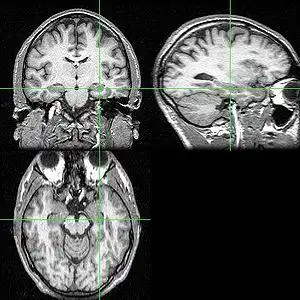

海马体在人脑中的位置

海马体在大脑中的位置由于杏仁核在大脑皮层的旁边,紧靠着储存记忆的

科学家通过对海马体的解剖发现,它在大脑中的长度不到10cm,之所以一